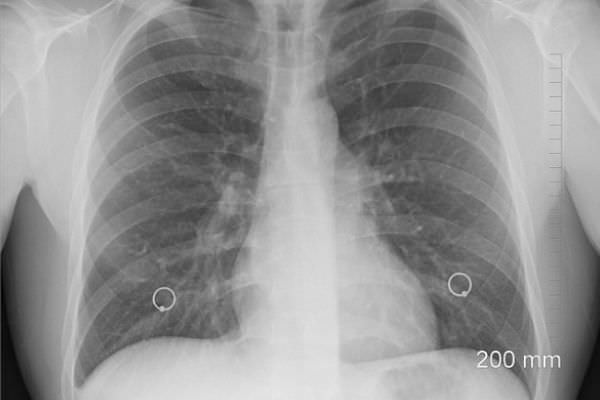

Сегодня прохождение флюорографии 1 раз в год всеми гражданами страны является обязательной процедурой, которая позволяет на самых ранних стадиях диагностировать такие патологии, как туберкулез, рак легких и др. Особенно это важно для курильщиков с большим стажем уничтожения собственного организма.

Благодаря этому методу диагностики удается своевременно выявлять нарушения, требующие немедленного лечения и спасения жизней больных. Флюорография помогла многим людям не только избавиться от тяжелых недугов, но и побороть никотиновую зависимость. Известны случаи, когда только одного взгляда на снимок собственных легких, пораженных многолетним потреблением никотина, хватало человеку для того, чтобы навсегда отказаться от сомнительного удовольствия.

Уникальность флюорографии заключается в том, что независимо от того, курили ли вы перед исследованием, на снимке будет видно все до мельчайших деталей.